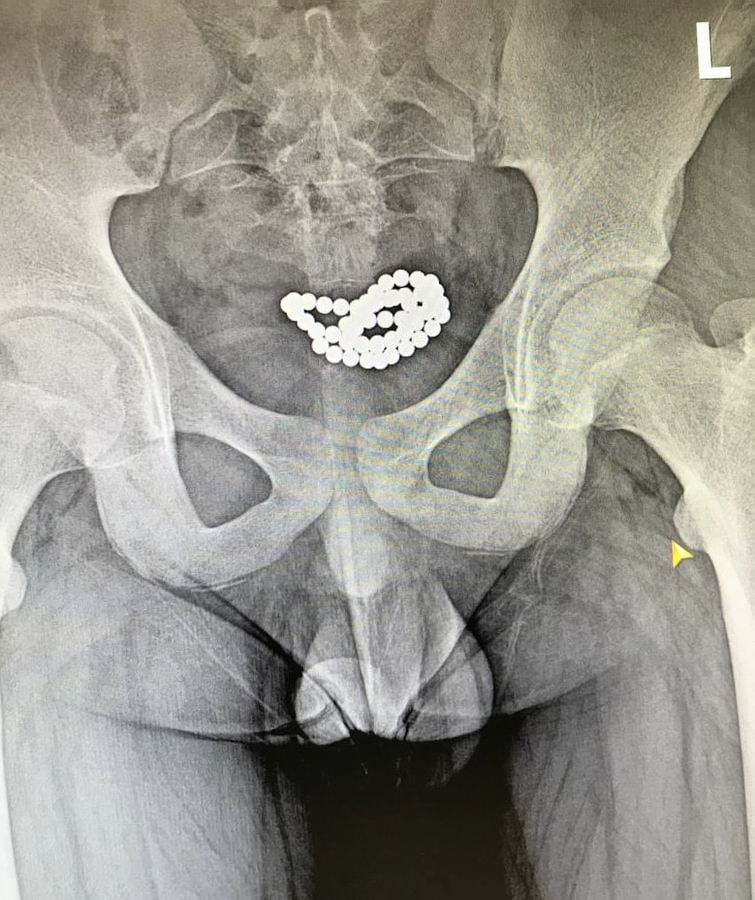

У нашому закладі успішно було прооперовано два ідентичних випадки евакуації магнітних кульок з сечового міхура хлопчиків у віці 10-15 років. В обох випадках була виконана цистотомія міні-лапаротомним доступом з подальшим вилученням 62 і 24 магнітних кульок,

На фото лікарські знімки, на яких видно, чим загрожує необережне поводження з іграшками.